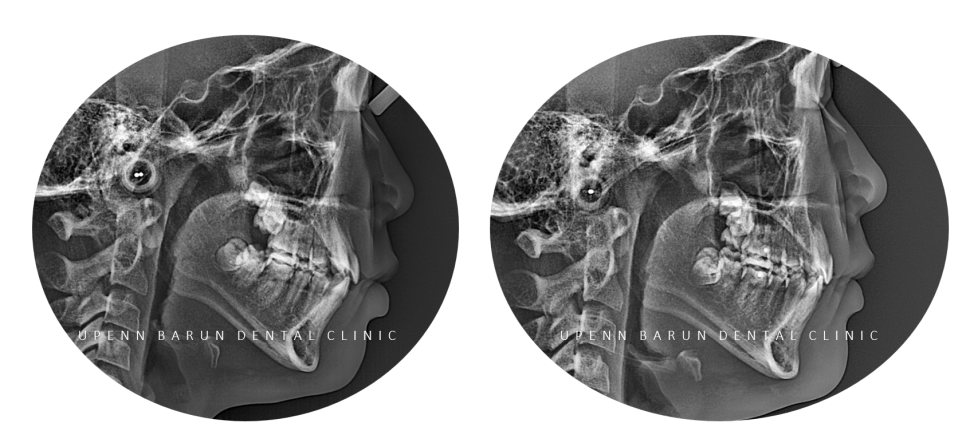

교정기간: 23/8 ~ 24/11

반대교합이 있던

앞니가 제 위치를 찾고

삐뚤빼뚤했던 치열이 가지런해진 모습을 확인해볼 수 있습니다.

교정기간: 23/8~ 24/1

25개의 장치를 통해 첫번째 클린체크를 마친후의 사진입니다

첫번째 클린체크만으로도 완성도 있게 교정이 잘 되었습니다 :)

다이아몬드등급의 치과답게

앞니의 반대교합은 3개월만에 개선이 되었다는 사실!!

앞니의 반대교합이 있고

치열이 고르지 않아

송곳니가 도드라져 보였던 이전과는 달리,

청소년기 인비절라인 교정 후 치열이 가지런해지면서

보다 정돈된 이미지를 줍니다.